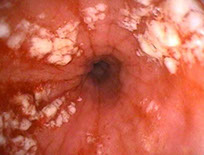

See multiple mucosal rings (linear furrows), esophageal trachealization, feline esophagus, white mucosal specs or normal on endoscopy

Eosinophilic esophagitis